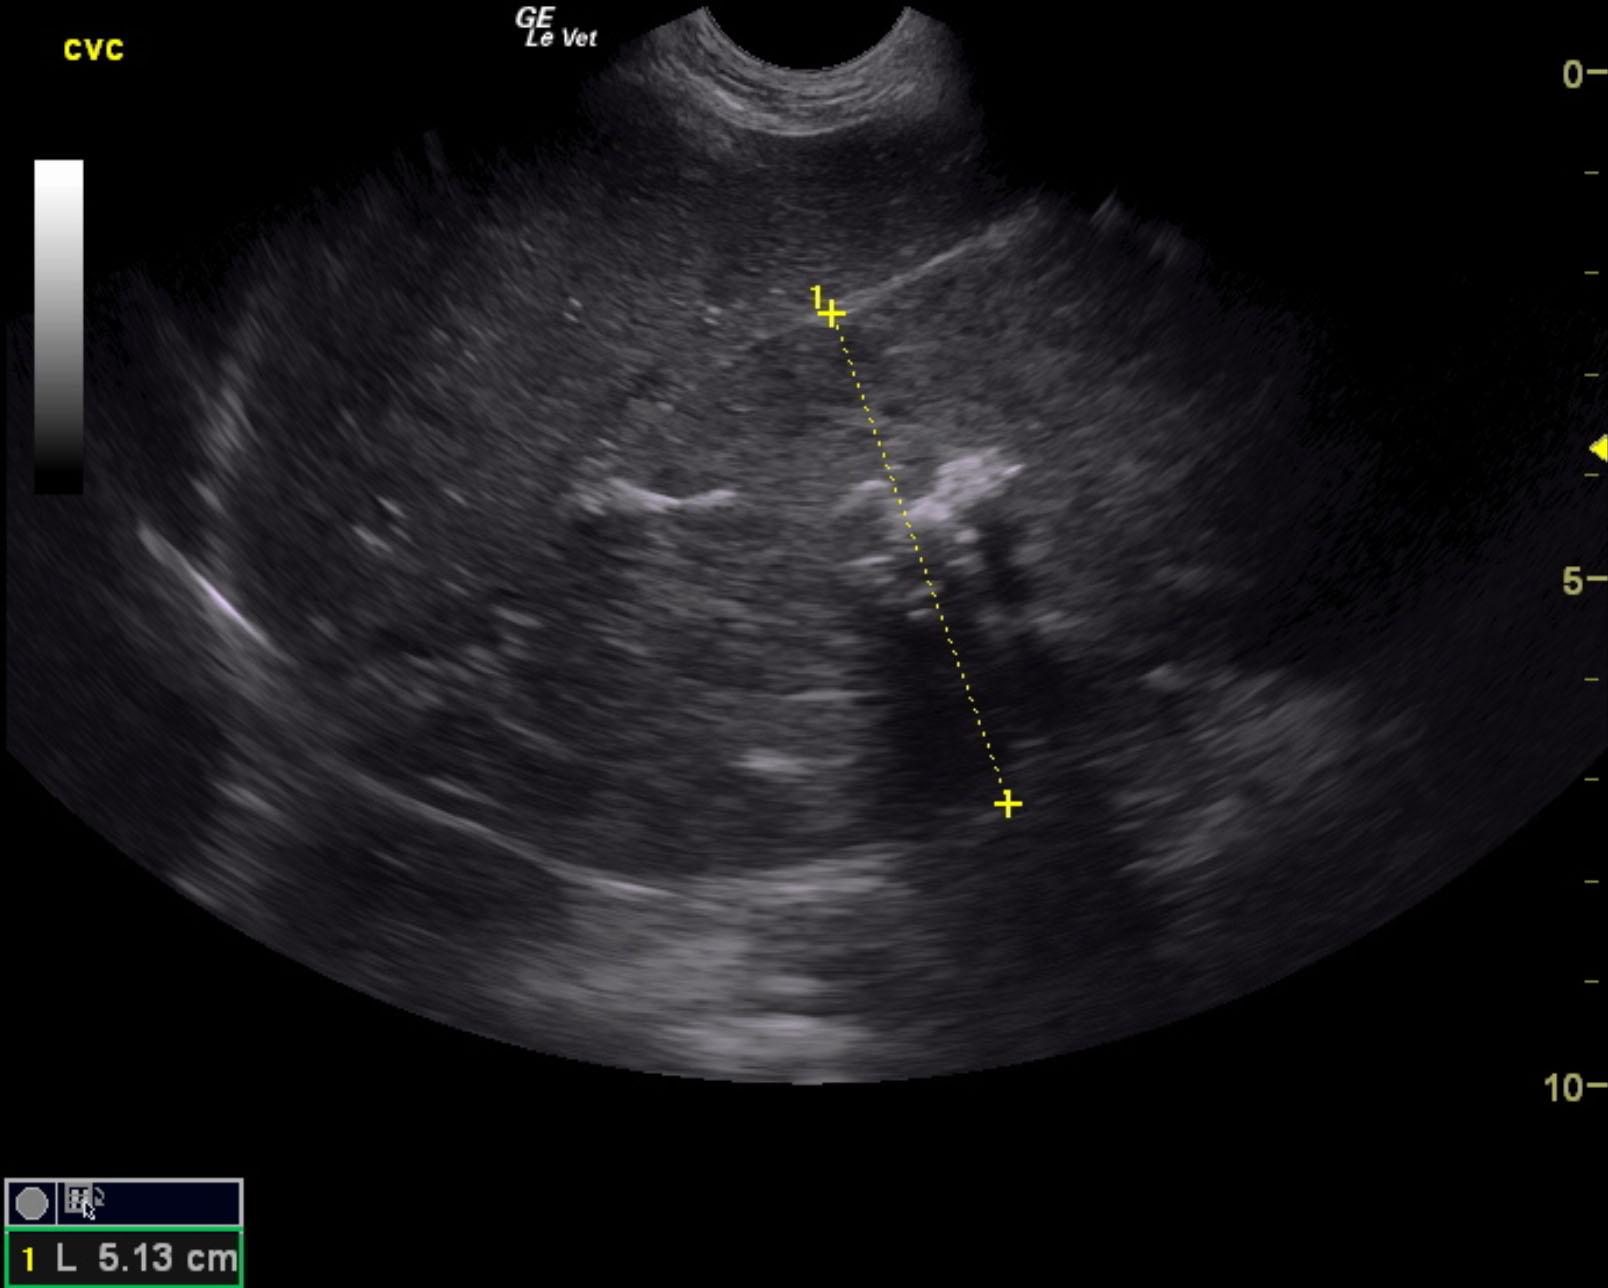

A 7-year-old FS mixed breed dog was presented for evaluation of weight loss and PU/PD. Abnormalities on blood work were neutrophilia, mild hypoglycemia (49), hyperglobulinemia, and elevated cobalamine.